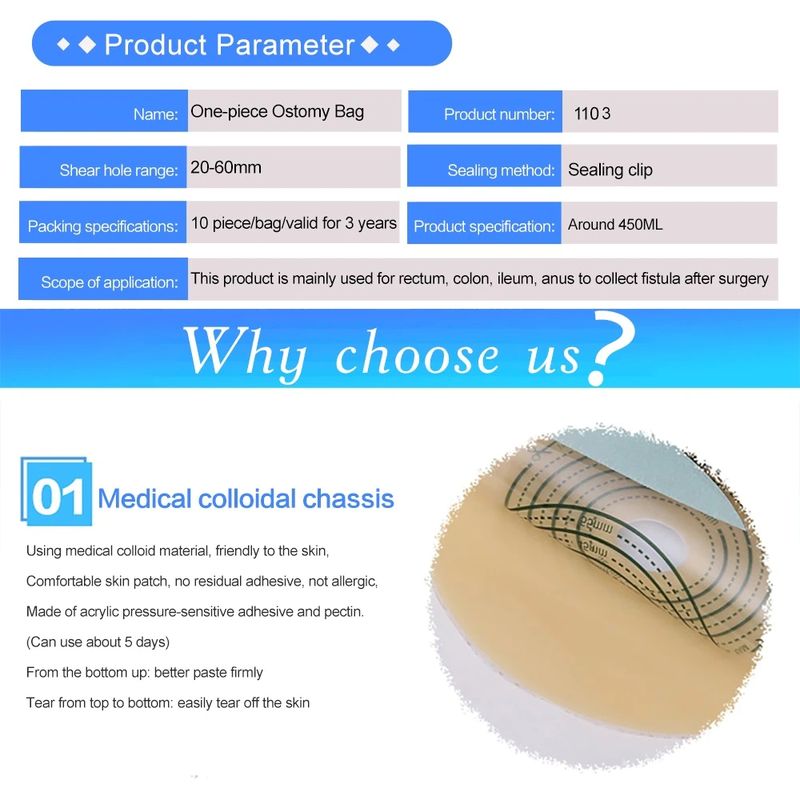

10 Uds. Bolsas de ostomía de sistema de una pieza bolsa de colostomía drenable estoma de ostomía 60mm Tamaño de corte Beige cubierta bolsa de orina con cierre de Clip

Descripción del producto La bolsa de cuidado de ostomía combina la barrera de la piel y la bolsa de colección en un sistema simple y fácil de administrar, proporcionando una gran simplicidad. La bolsa de colostomía es fácil de aplicar con el cierre de Velcro adjunto, proporcionando seguridad, ya que los sujetadores de plástico se bloquean en su lugar, fáciles de vaciar y irrigar. El propósito de reemplazar la ostomía 1. Observa la mucosa del estoma, las suturas circundantes y la piel circundante. 2. Limpia la piel alrededor del estoma, reduce el olor y aumenta la comodidad. 3. Evita que el agua fecal contamine la incisión abdominal a través de la fuga del chasis. 4. Si hay impregnación, asegúrese de reemplazarla a tiempo. Se recomienda cambiar el tiempo de 3-5 días para garantizar una respiración efectiva de la piel. Sentido común de la vida ostomía 1. Comer uniformemente, beber mucha agua y comer más verduras y frutas. 2. Evite comer demasiado rápido y tragar aire, masticar alimentos lentamente, Evite hablar mientras come, evite comer demasiado de una vez. 3. Evite las comidas con alto contenido de fibra y evite el bloqueo del estoma. 4. La ropa es suave y cómoda. 5. Evita el trabajo para aumentar la presión abdominal (como extraer objetos pesados). 6. Mantenga su estado de ánimo feliz. Paquete 10 unids/caja bolsa de ostomía